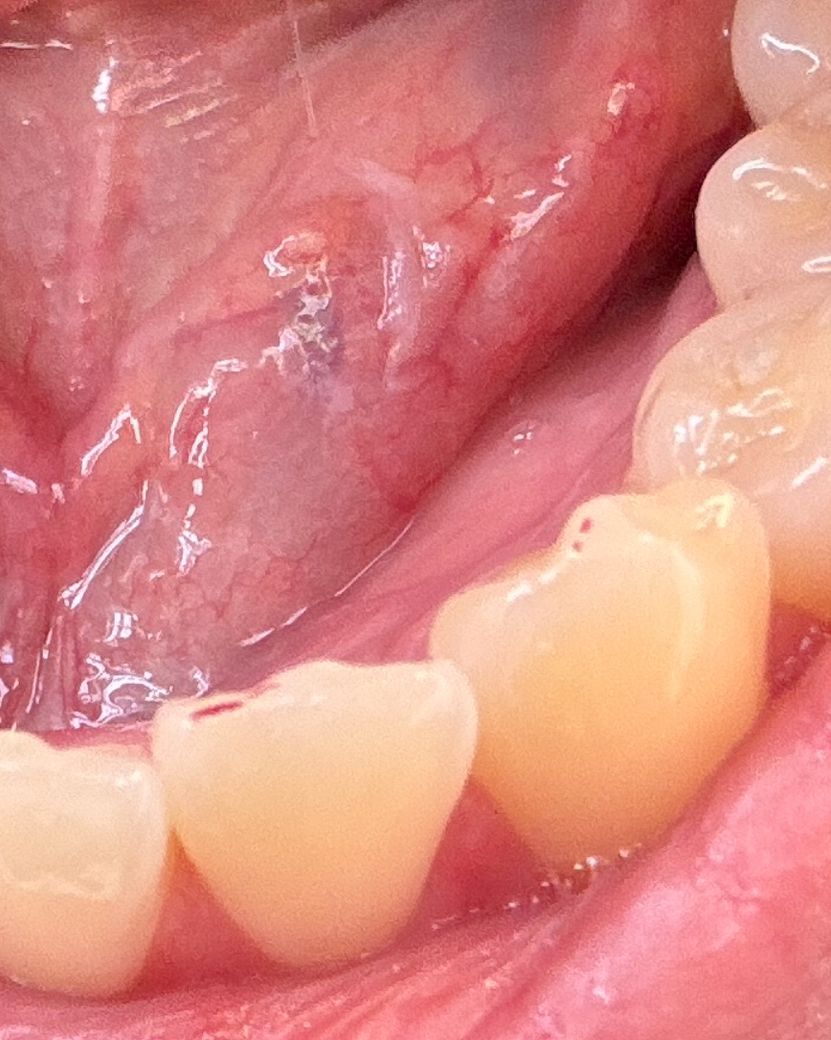

얼마전 오돌뼈를 앞니로 잘못씹은후 앞니에 계속 통증이 있어 병원에 다녀왔는데 엑스레이상 별 문제가 없었습니다 또한 밑에 이와 닿을때마다 밀리는느낌이 있어 교합도 봐달라했는데 이정도면 조정은 안해도될것같다 하시는데 저는 무리하게 닿는것 같아서요ㅜㅜ 교합점으로 한번 봐주실수있나요 첫번째사진이 앞니 안쪽부분 두번째사진이 밑에 앞니옆이빨 사진입니다. 교합점이 앞니에서 저렇게 찍히는게 정상인가요?

• 1번 째 사진

• 2번 째 사진

사람마다 교합점이 찍히는 위치는 차이가 있을 수 있습니다 오돌뼈와 같이 단단한 음식을 먹게 되어 치아의 충격이 가해졌다면 일시적으로 통증이 있을 수 있습니다.